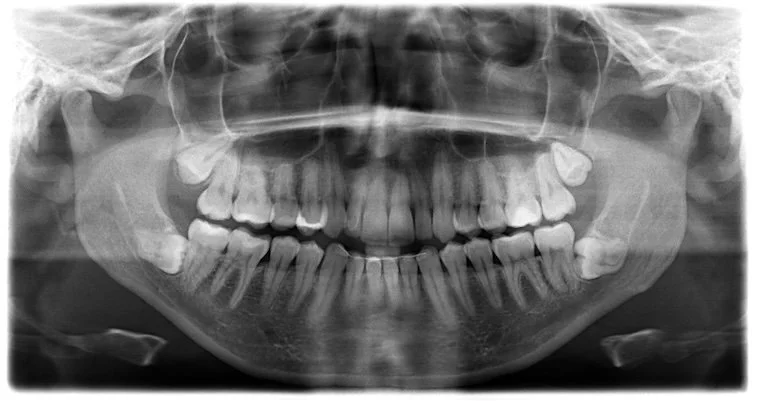

1. Consultation & X-rays – We’ll assess your tooth, explain your options, and ensure you understand the procedure.

Tooth extraction Margaret River

• Careful assessment using dental X-rays